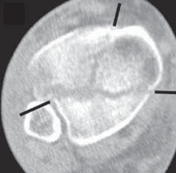

22.

Cole et al3 mapped 38 consecutive AO/OTA 43-C3 (complex articular) plafond fractures with CT scans and found that all plafond fractures in this category exited the tibiofibular joint laterally and at two separate locations medially to create a coronally oriented Y pattern with three major fragments ( FIG 2A). There were also varying amounts of articular comminution anterolaterally or anteromedially (FIG 2B).

--- A B ### FIG 2 • A,B. CT images from 43-C3 plafond injuries demonstrating typical fracture patterns with anterolateral, medial malleolus, and posteromedial fragments. Variable amounts of central or anterocentral articular impaction and comminution are commonly seen.

1. Isolated osteochondral fragments of variable size are often encountered (typically central to anterolateral in location; Fig 2B) and constitute the remaining portion of the articular surface.